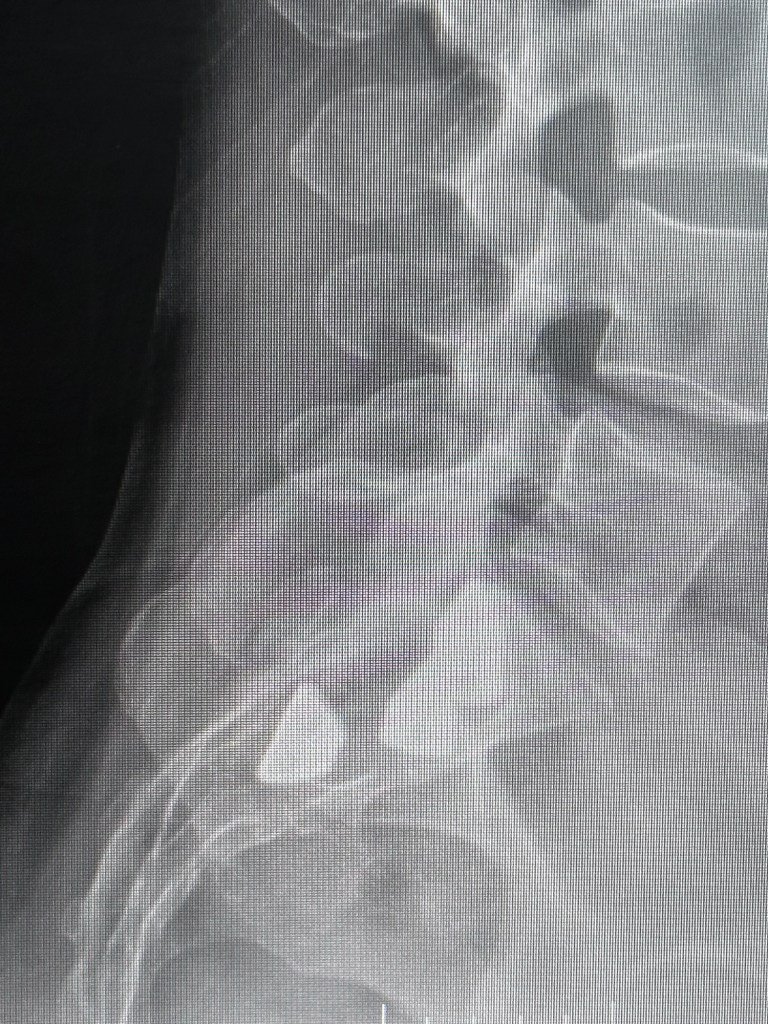

Anterior View of the three SI joint implants